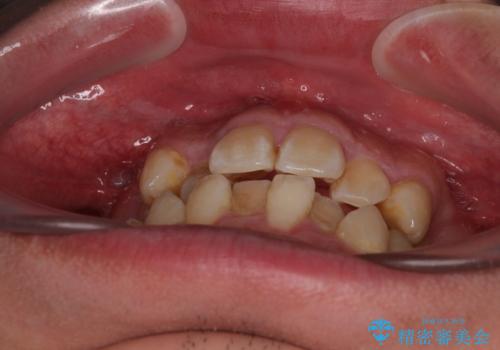

診査の結果、上下前歯に強い叢生が認められ、歯をきれいに並べるためのスペースが明らかに不足していました。

無理に歯を並べると、前歯が前方に突出するため、抜歯によるスペース確保が必要と判断しました。

上下左右の小臼歯を抜歯し、歯列を整えるためのスペースを確保

左下は第二小臼歯に根管治療歴があったため、左下のみ第二小臼歯を抜歯しアンカースクリューを併用

それ以外の部位は第一小臼歯を抜歯